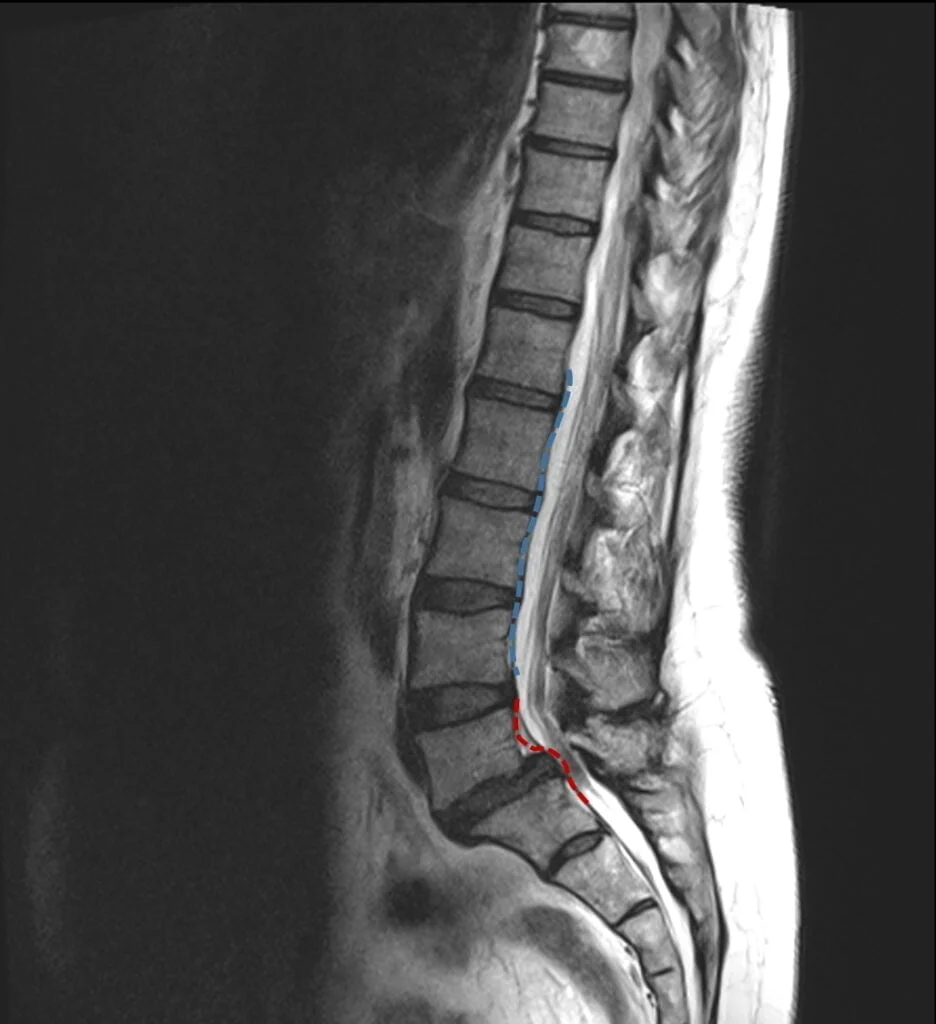

À droite : exemple de spondylolisthésis (en pointillés rouges) à comparer à l’alignement normal des vertèbres (pointillés bleus).